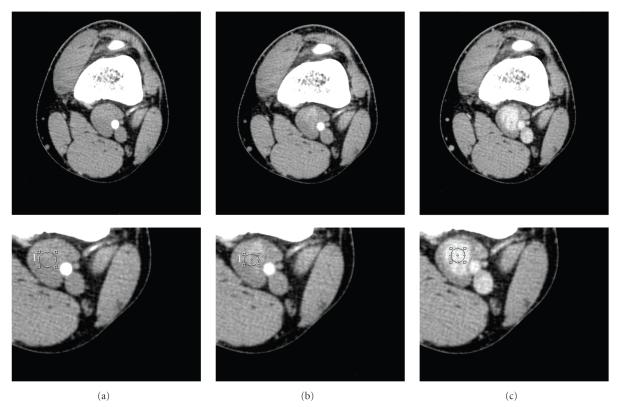

We report a case of a 21-year-old man with a popliteal venous aneurysm of the left popliteal fossa, with local symptoms and pain during palpation. Early diagnosis is fundamental in order to prevent the thromboembolic events or other major complications. Duplex scanning, Computed Tomography scanning, and Magnetic Resonance imaging are considered to be important non-invasive diagnostic methods for the diagnosis of PVA. The Angio Computed Tomography acquisition confirmed a 36 mm x 17 mm oval mass in the left popliteal fossa continuous with the popliteal veins. This lesion had presented contrast enhancement only in delayed acquisition (180 sec) and so appeared to be a true venous aneurysm and no arterial. The PVA was repaired surgically via a posterior approach to the popliteal fossa. A 4 x 2 aneurysm was identified. In the same time open tangential aneurysmectomy and lateral vein reconstruction were realised. This case is interesting because the Angio Computed Tomography study, in delayed acquisition, has allowed a correct diagnostic assessment of PVA and the surgical treatment.

我们报告一例21岁男性患者,其左腘窝患有腘静脉瘤,伴有局部症状及触诊疼痛。早期诊断对于预防血栓栓塞事件或其他严重并发症至关重要。双功扫描、计算机断层扫描和磁共振成像被认为是诊断腘静脉瘤的重要无创诊断方法。血管计算机断层扫描成像证实左腘窝有一个36毫米×17毫米的椭圆形肿块,与腘静脉相连。该病变仅在延迟采集(180秒)时出现对比增强,因此似乎是一个真正的静脉瘤而非动脉瘤。通过腘窝后方入路对腘静脉瘤进行了手术修复。发现一个4×2的动脉瘤。同时进行了开放性切线动脉瘤切除术和外侧静脉重建。该病例很有意思,因为血管计算机断层扫描研究在延迟采集时能够对腘静脉瘤进行正确的诊断评估并指导手术治疗。